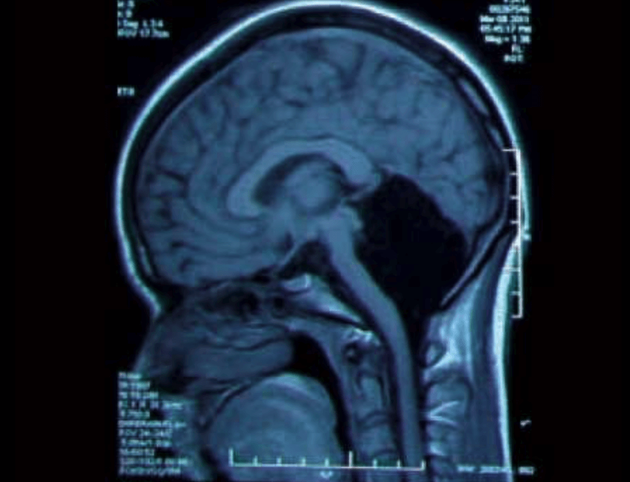

北京时间12月16日消息,2014年,中国一名24岁的女士因持续一个月的头晕和呕吐而入院。她对这些症状并不陌生,因为她一直都无法稳步行走,而且几乎生来就饱受头晕之苦。这些都是十分严重、令人虚弱的症状。然而,从CT和核磁共振(MRI)扫描的诊断结果来看,这些症状甚至可以算十分轻微;医生发现,这位女士缺失了大部分的大脑,确切的说,她缺失了小脑。

2014年,中国一名24岁的女士因持续一个月的头晕和呕吐而入院。医生通过对她的大脑扫描发现,她缺失了小脑